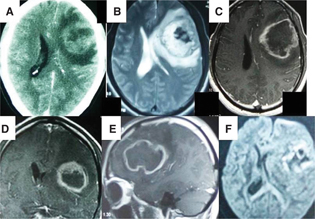

Neuroimaging plays an important part in the diagnosis, management, and prognostication of GBMs. Computed tomography (CT) and magnetic resonance imaging (MRI) form the backbones as far as the radiological assessment of these tumors is concerned. On CT and conventional sequences of MRI, these tumors appear as irregular, heterogeneously contrast-enhancing masses with significant perilesional edema. Although, some of the anaplastic astrocytomas may not enhance, GBMs almost always enhance. Necrosis, hemorrhage, and a garland pattern of enhancement are often characteristic of GBMs. The common differential diagnosis includes metastasis, lymphoma, brain abscess, etc. Although contrast-enhanced computed tomogram is usually characteristic, MRI provides finer details needed for surgical as well as radiotherapy (RT) planning. Magnetic resonance spectroscopy typically displays choline peak with reduced N-acetyl aspartate in the region of the tumor although no such peaks may be seen in areas of necrosis. Diffusion-weighted images may show restricted diffusion with low apparent diffusion coefficient in the cellular parts of the tumor. While contrast images delineate the portions of the tumor with blood–brain barrier disruption, T2 fluid-attenuated inversion recovery (FLAIR) images clearly demonstrate the nonenhancing and edematous portions. Figure 1 shows the different radiological characteristics of GBM. Apart from the above diagnostic information, recent MRI techniques like functional MRI, tractography, etc., help in planning tumor resections, especially in eloquent locations. Perfusion-weighted MRI, although not routinely used, shows increased vascularity inside the tumor, a characteristic feature in high-grade gliomas. It can be performed by utilizing one of the three techniques, namely, magnetic resonance perfusion imaging, dynamic susceptibility contrast-MRI, and dynamic contrast-enhanced MRI (48).

Fig 1

Figure 1 (A). Post-contrast computed tomography of the head shows a left frontal irregularly enhancing intraaxial mass of size approximately 4.5 × 4.5 cm with perilesional edema. The mass is causing effacement of the adjacent lateral ventricle. The mass is heterogeneously hyperintense on T2-weighted image with central necrosis (B). The peritumoral edema and ventricular compression is well made out on T2 images (B). The mass shows peripheral and ring-like contrast enhancement (C, D, E). The peripheral enhancing part shows hyperintensity on diffusion-weighted films suggestive of diffusion restriction (F). (The image was taken in 3T MRI scanner, GE, USA.)